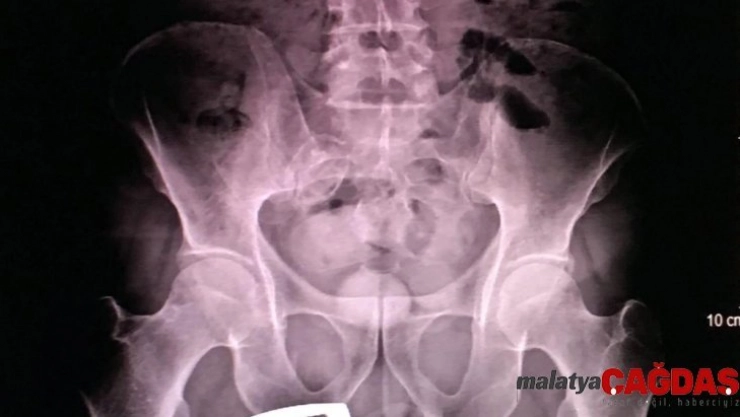

Erzurum Emniyet Müdürlüğü Kaçakçılık ve Organize Suçlarla Mücadele (KOM) Şubesi ekipleri, uygulama sırasında durdurdukları bir yolcu otobüsünde arama yaptı. İranlı B.H.’ye ait olduğu anlaşılan valizde, 21 parçadan oluşan ve ‘met’ olarak bilinen 607 gram ‘metamfetamin’ maddesi ele geçirildi. Gözaltına alınan B.H.’nin hareketlerinden şüphelenen narkotik polisi, kendisini sağlık kontrolü için hastaneye götürdüğünde röntgen çekilmesini de istedi. Röntgen filmi sonuçlarında İranlı kadının uyuşturucuyu kapsüller halinde makatına soktuğu anlaşıldı.

Tıbbi müdahaleyle 4 kapsül halinde 96 gram ‘met’ ve bir kapsülde 28 gram reçine esrar çıkarılırken, uyuşturucunun piyasa değerinin 50 bin lira olduğu belirtildi. İranlı B.H. tutuklanarak cezaevine konuldu.